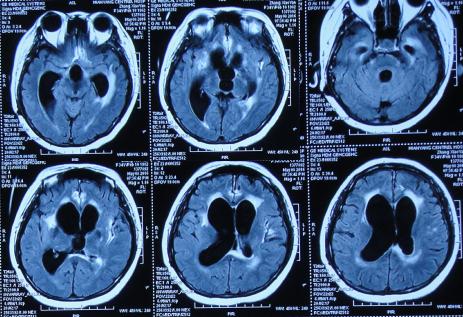

2016年6月3日住入李小勇脑脊液中心,入院时:卧床,反应慢,表情淡漠,言语迟钝(问答无反应),吞咽困难,只能鼻饲流食,头部有多处手术疤痕,右下肢自主活动差,但刺激后能动(图-25);入院第2天即2016年6月5日,头部CT示脑积水,脑室粘连,脑萎缩(图-26)。

图-26:2016年6月5日头部CT入院时

入院后4天即2016年6月7日,进行了脑室腹腔分流管取出术+脑室腹腔分流泵取出术+脑室外引流术+脑室腹壁外引流术+透明隔造瘘术,术后当天查头部CT示脑室引流术后(图-27)。

图-27:2016年6月7日术后头部CT